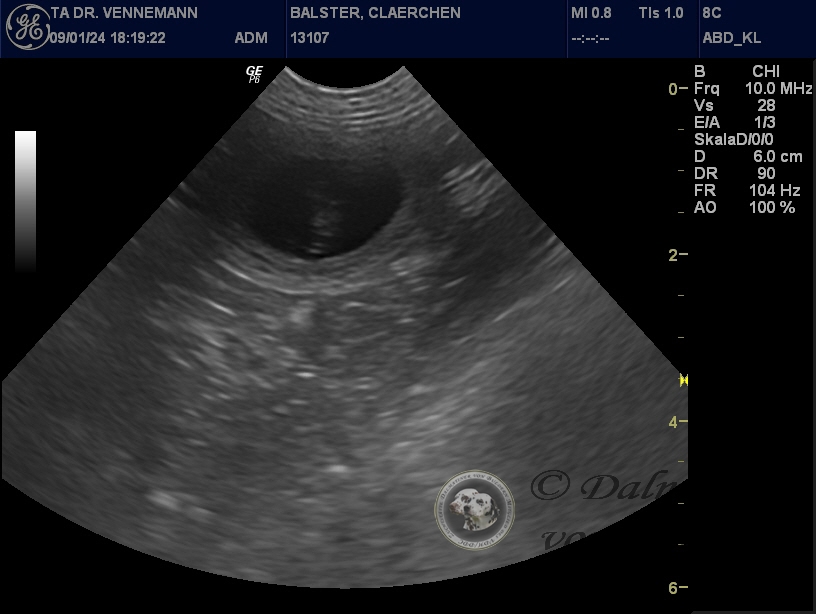

Nachdem wir im Ultraschall deutlich das pochernde Herzchen eines Fötus gesehen hatten und unser Tierarzt noch eine weitere Fruchtanlage vermutete - hat das Kontrollröntgen wenige Tage vor dem errechneten Geburtstermin ergeben, dass Clärchen resorbiert hat! Es war nix mehr zu sehen von Welpen - der Uterus war noch ein wenig angebildet, aber Welpen waren nicht mehr vorhanden.